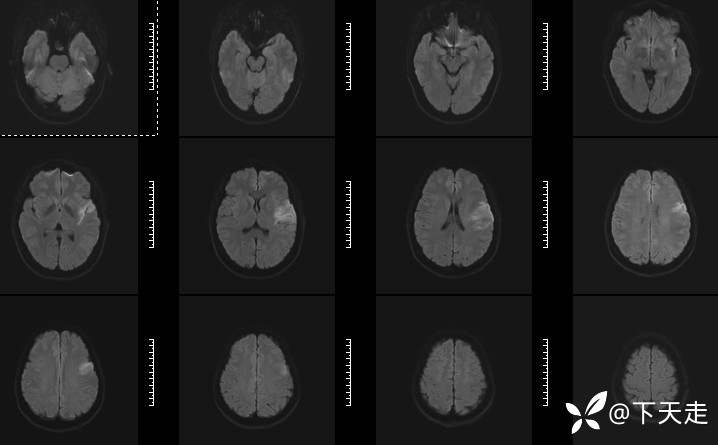

青鹊词 推荐青年女性,37岁,因不能言语就诊于耳鼻喉科,耳鼻喉科医生诊疗后建议神经内科就诊。

查体:神清,完全性运动性失语,四肢肌张力正常,肌力5级。

相关检验检查资料如下

给予阿司匹林肠溶片,硫酸氢氯吡格雷片抗血小板聚集,阿托伐他汀钙片调脂稳斑,丁苯酞注射液促进侧支循环建立,线粒体保护等治疗,治疗14天,好转出院,可与人进行言语交流。